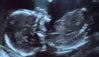

Noe veldig også, sparket og kavet med armeneHurra for en aktiv gutt![]()